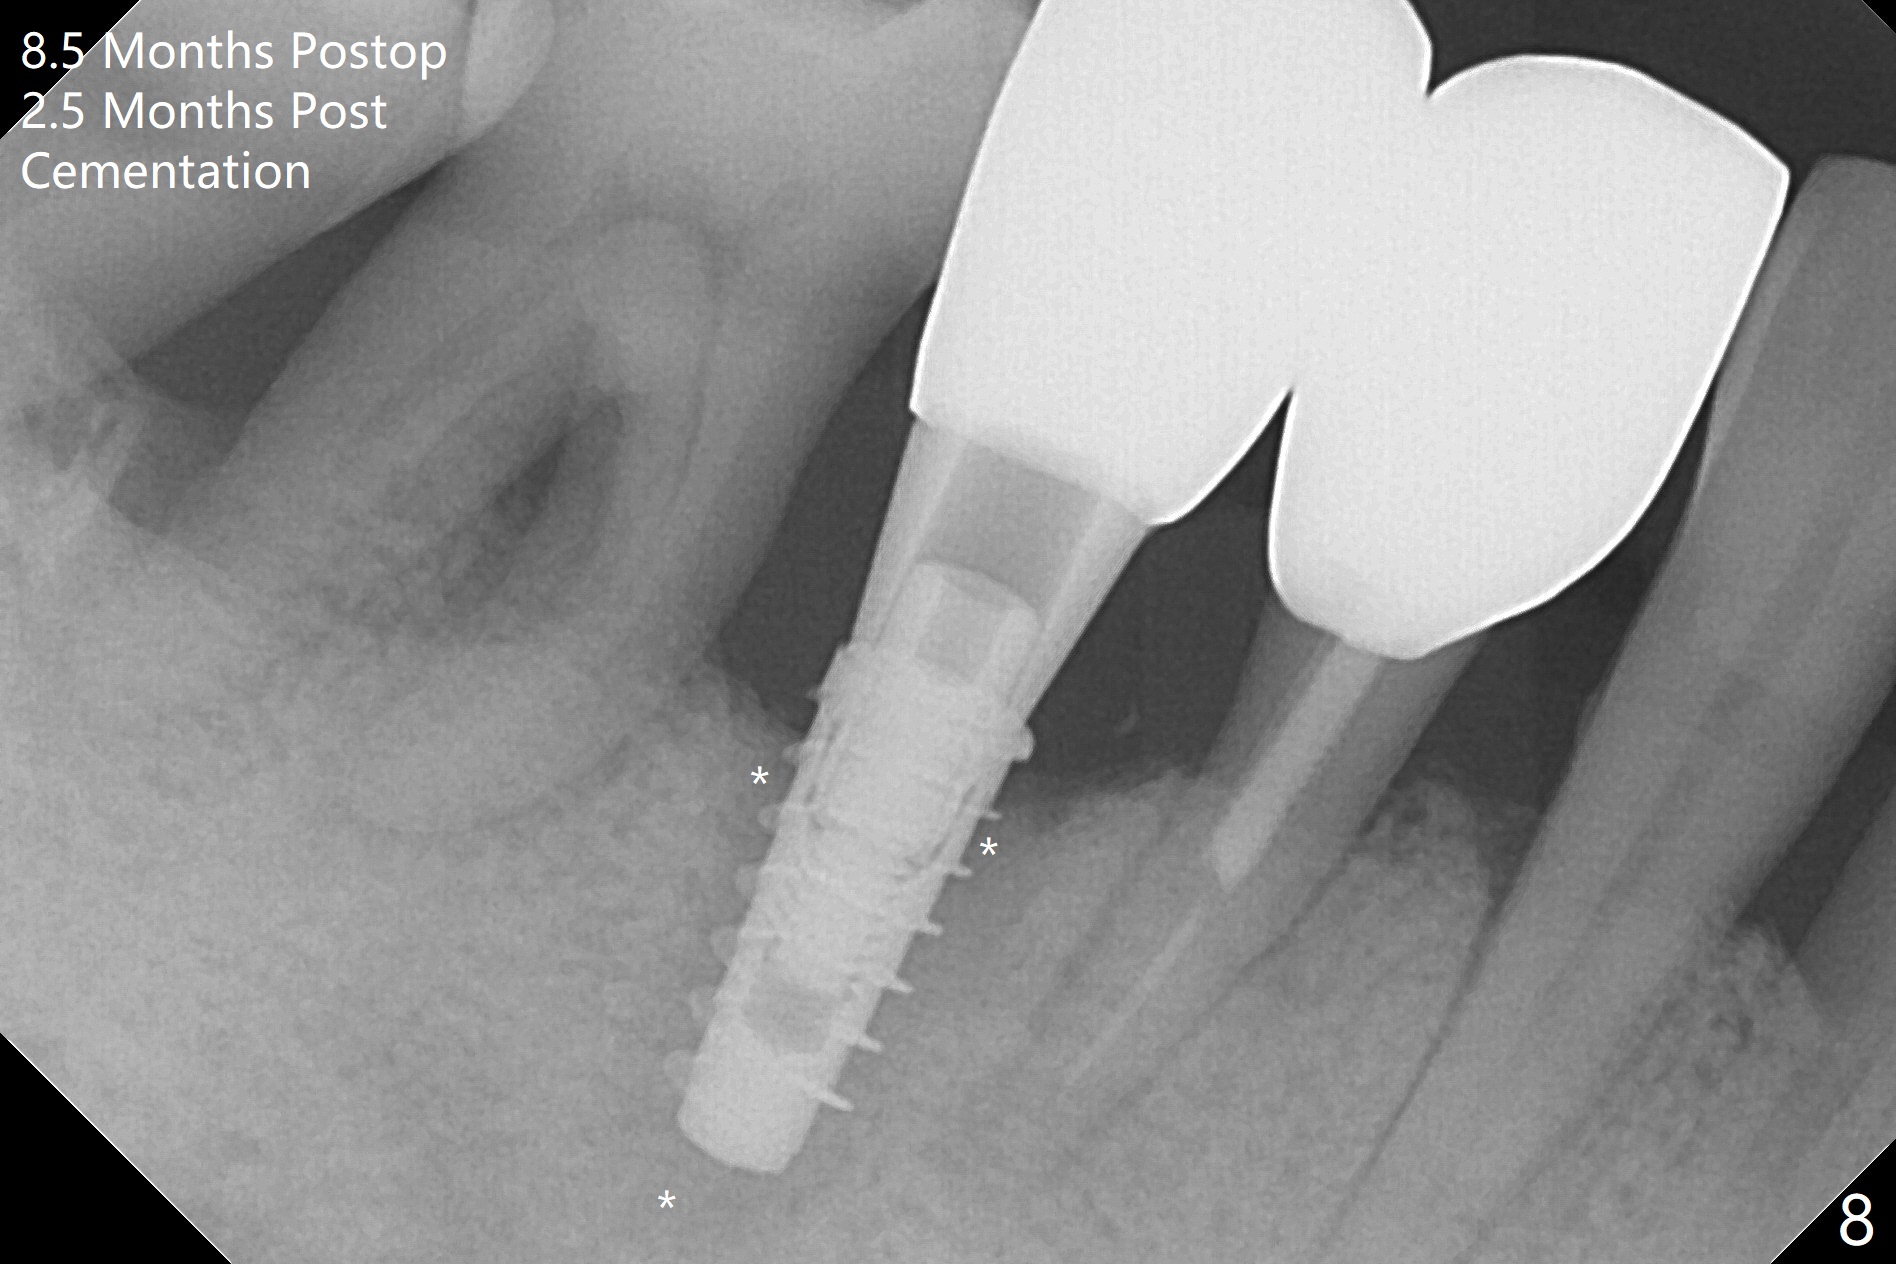

The tooth #29 is easily extracted with granulation tissue attached to the apex (Fig.1,2). The buccal plate is low. Initial osteotomy is established in the mesial slope of the socket for 13 mm subgingival (Fig.3 red dashed line). After adjustment of the osteotomy position and use of Magic Drills 2.8 and 3.3 mm for 15 mm subgingival, a 4x9 mm dummy implant is placed 2 mm subgingival (Fig.4). Final implant (Fig.5: 4x9 mm; red dashed line: socket) is placed 4 mm subgingival (supracrestal buccal; infracrestal lingual); Vanilla graft placed buccodistal (*). With placement of a 4.5x5.7(4) mm abutment (Fig.5), an infraocclusal immediate provisional (Fig.6 P) is fabricated to maintain the interdental papillae. One month later, the abutment dislodges. The patient insists upon no provisional so that he can masticate on the right side, since there is no functional molars on the left side. The implant appears to have osteointegrated 5 months postop (Fig7). The crown is loose 2.5 months post cementation (8.5 months postop); there is bone loss around the implant (Fig.8 *). Vanilla graft is placed after implant removal (Fig.9); in fact the neighboring teeth also have mobility (including periapical radiolucency at #30 (Fig.9 *)).